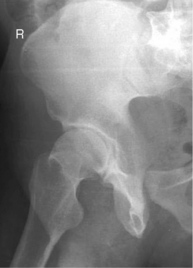

(Axiolateral Inferosuperior Projection [Danelius-Miller Method])

• Supine, no rotation of pelvis

• Flex unaffected knee and hip and provide support such as the x-ray tube (use pad or towels for possible hot collimator).

• Rotate affected leg internally 15° unless possible hip fracture.

• Place vertical grid IR against side just superior to iliac crest with plane of IR perpendicular to CR.